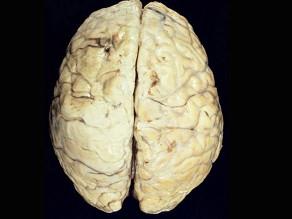

问题 观察图片所示病理,流脑脑膜炎期的病变特点下列说法正确的为 ( )

选项 A.早期能发生脑室孔阻塞 B.病变主要部位在软脑膜及蛛网膜 C.脑实质无炎症 D.颅底部炎症粘连可导致脑神经损害 E.硬脑膜水肿

答案 B